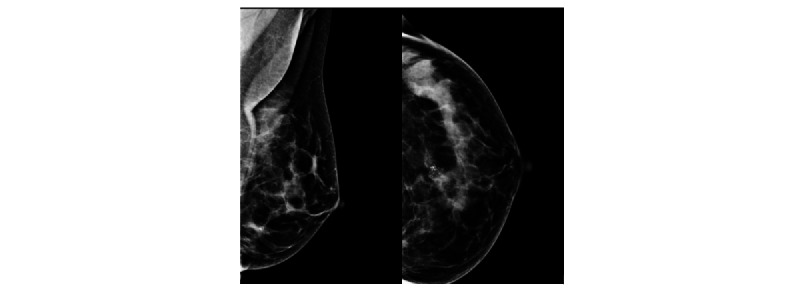

Methods: This is a retrospective study applying a commercial AI CAD system (Insight MMG, version 1.1.4.3; Lunit Inc) to a cancer-enriched mammography screening data set of 10,889 women (median age 56, range 40-74 years). The AI CAD generated a continuous prediction score for tumor suspicion between 0.00 and 1.00, where 1.00 represented the highest level of suspicion. A binary read (flagged or not flagged) was defined on the basis of a predetermined cutoff threshold (0.40). The flagged median and proportion of AI scores were calculated for women who were healthy, those who had a benign biopsy finding, and those who were diagnosed with breast cancer. For women with a benign biopsy finding, the interval between mammography and the biopsy was used for stratification of AI scores. The effect of increasing age was examined using subgroup analysis and regression modeling.